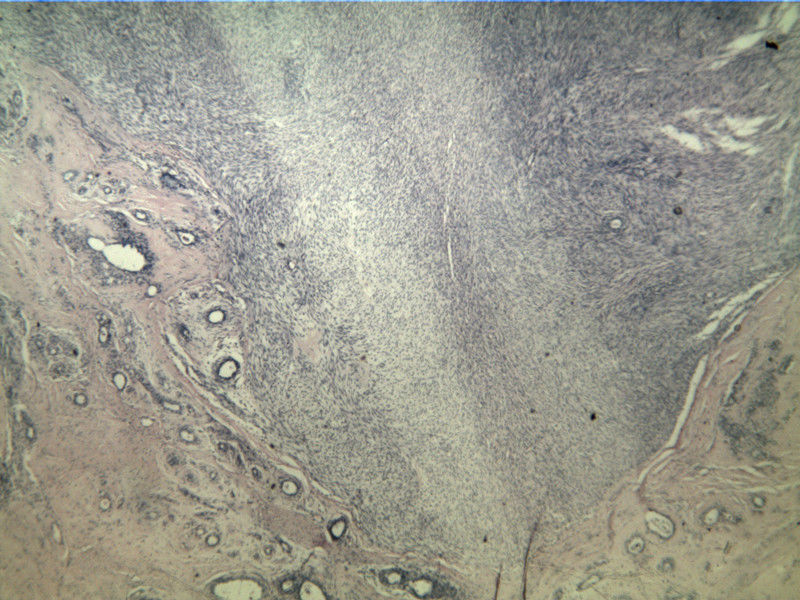

B3817

包块-有包膜(V3x3x2,39y)

叶状肿瘤 导管周间质肿瘤